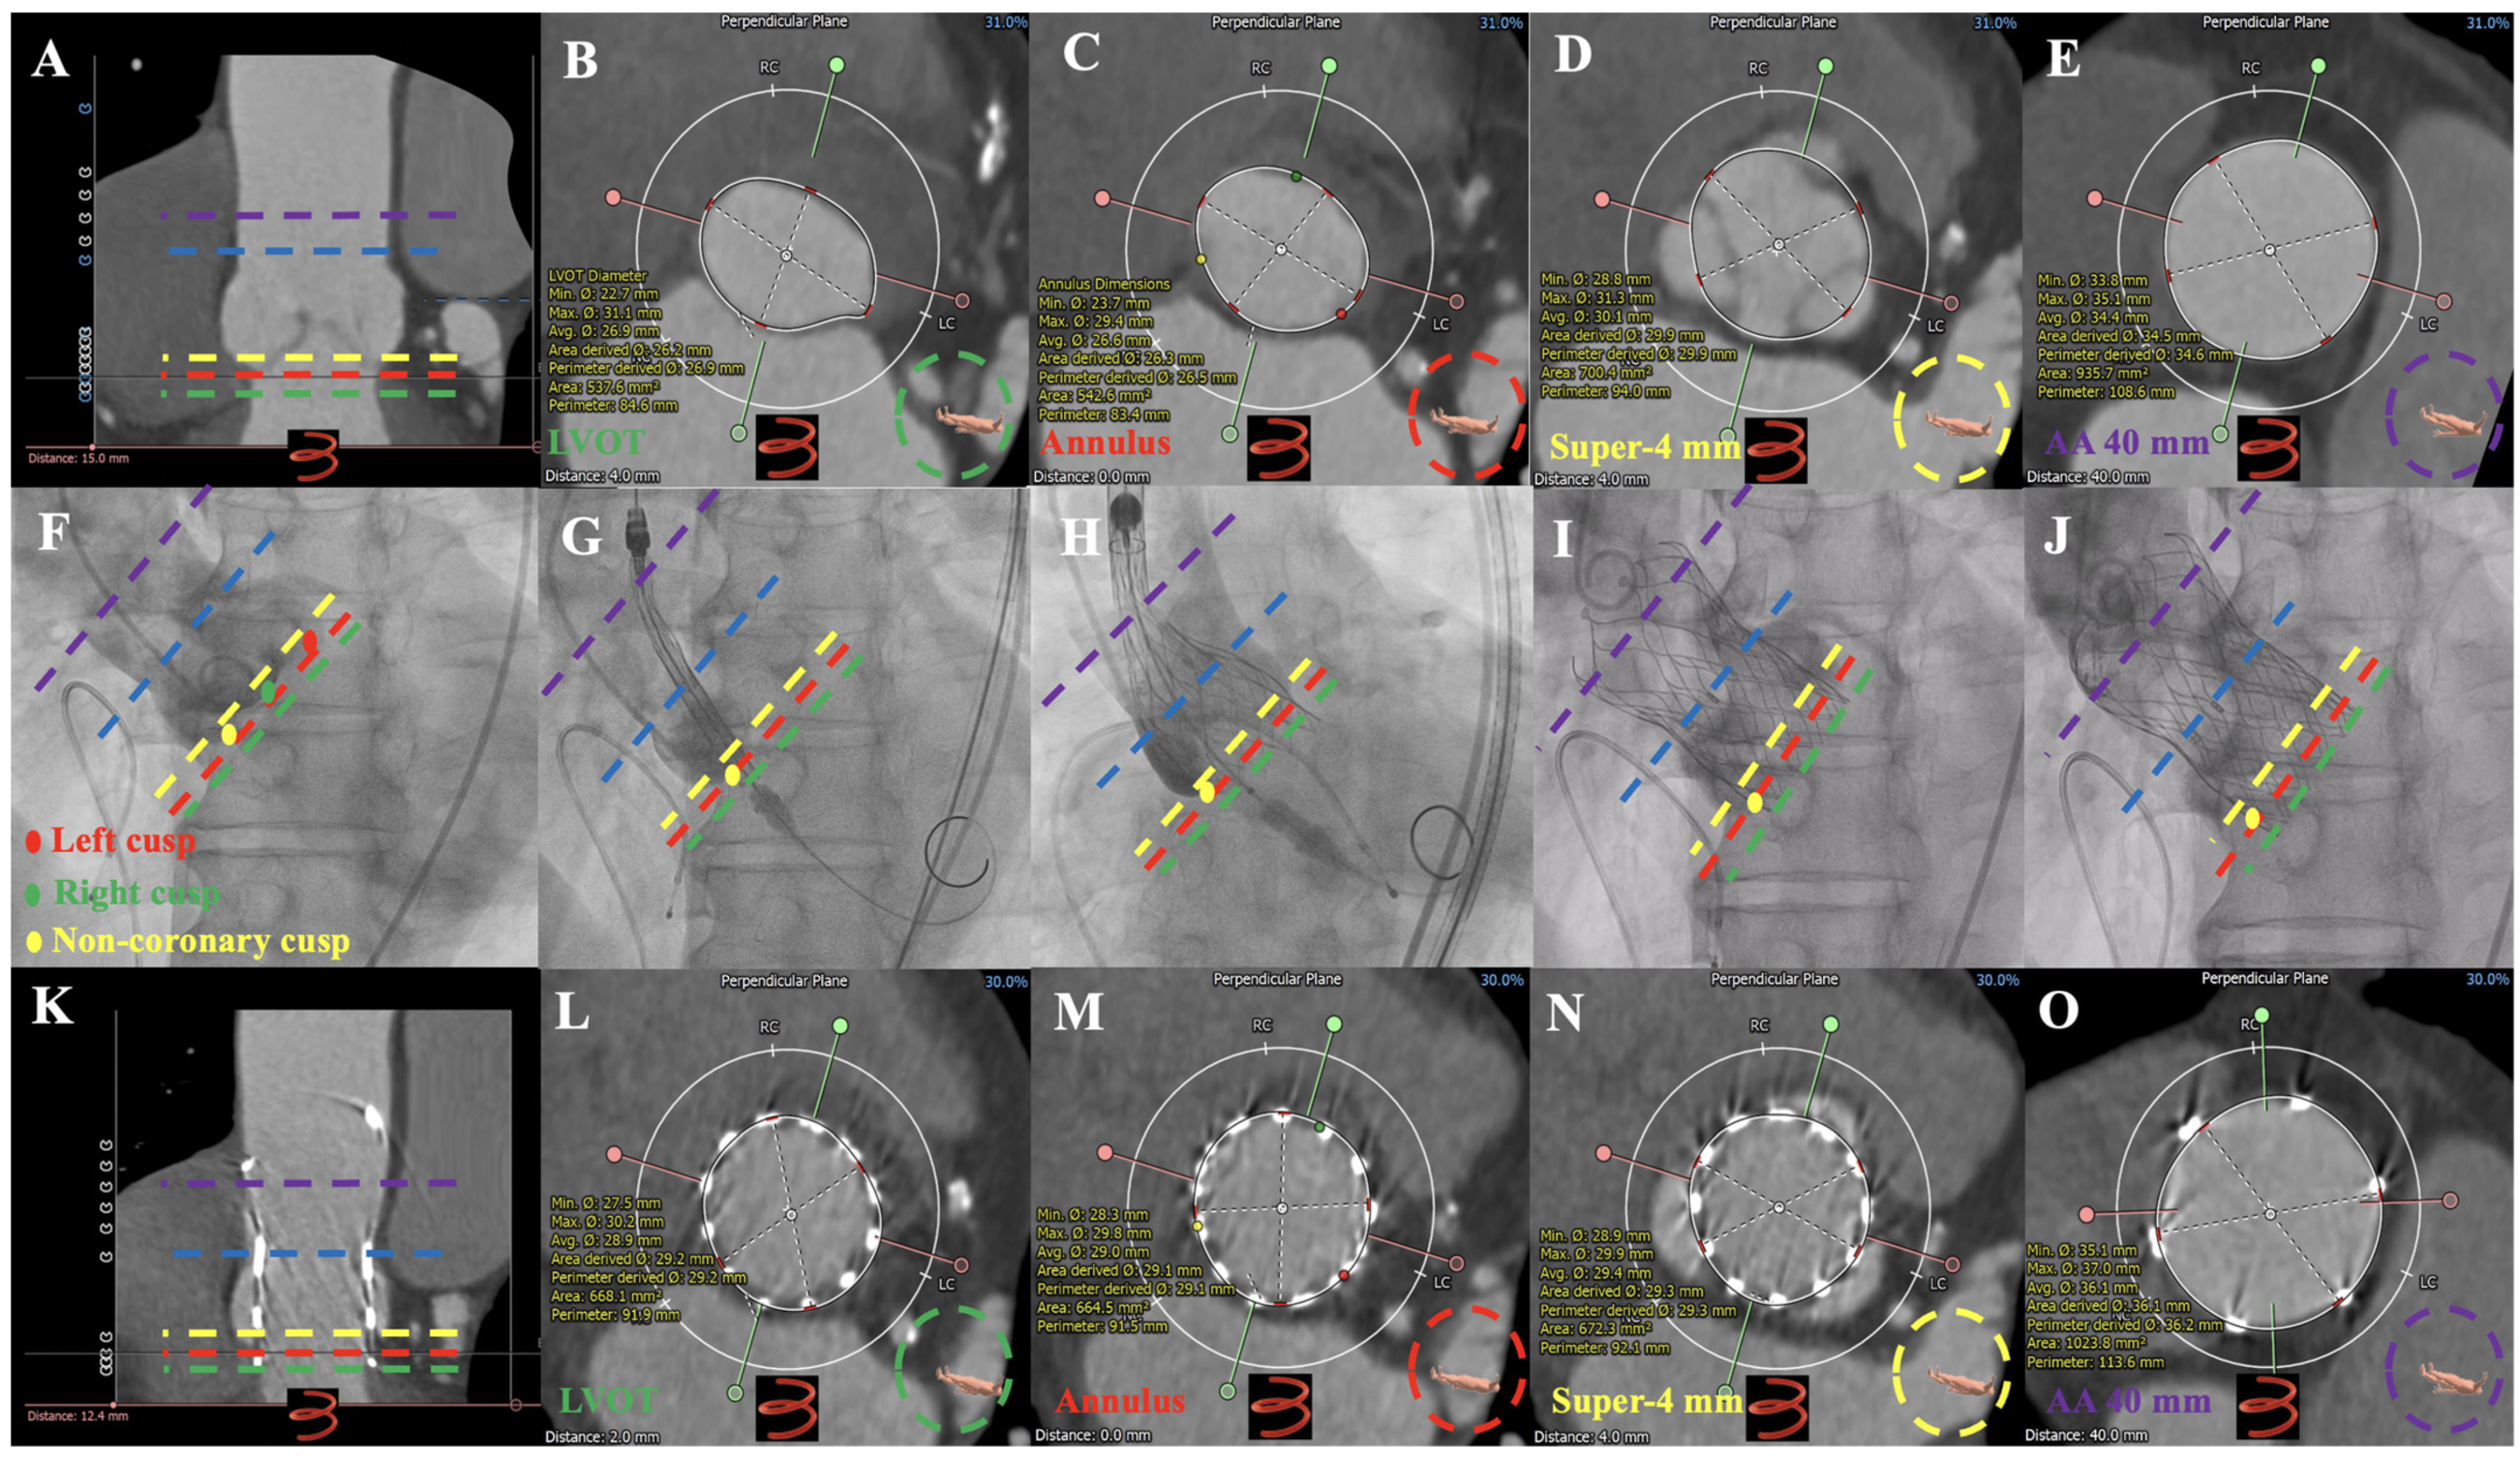

3.2. MDCT Evaluation and Anatomical Classification

| Dual-anchoring multiplane measurement (diameter calculated by the perimeter, mm) | ||||||

| Sup-2 mm | 26.2 ± 2.6 | 25.7 ± 1.7 | 27.5 ± 1.7 | 25.5 ± 2.3 | 29.3 ± 5.0 ac | 0.040 |

| Sup-2 mm | 26.7 ± 2.0 | 26.4 ± 1.6 | 27.9 ± 1.4 | 26.7 ± 2.3 | 26.8 ± 2.9 | 0.715 |

| Sup-4 mm | 28.3 ± 2.1 | 28.2 ± 1.8 | 29.4 ± 2.0 | 28.4 ± 2.5 | 27.0 ± 2.4 | 0.516 |

| Sup-6 mm | 29.6 ± 2.2 | 29.4 ± 2.0 | 31.1 ± 2.0 | 29.8 ± 2.2 | 28.0 ± 2.8 | 0.295 |

| Sup-8 mm | 30.5 ± 2.4 | 30.1 ± 1.7 | 31.8 ± 4.5 | 31.1 ± 2.5 | 28.8 ± 2.9 | 0.254 |

| Sup-10 mm | 31.2 ± 2.6 | 30.6 ± 1.8 | 32.4 ± 5.0 | 32.2 ± 2.6 | 30.0 ± 3.0 | 0.212 |

| Sup-min | 26.6 ± 2.0 | 26.4 ± 1.7 | 27.9 ± 1.4 | 26.7 ± 2.3 | 26.2 ± 2.9 | 0.686 |

| AA-30 mm | 37.7 ± 5.4 | 34.2 ± 2.8 | 36.1 ± 5.8 | 42.5 ± 5.2 ab | 38.5 ± 2.6 | 0.000 |

| AA-35 mm | 38.7 ± 5.4 | 35.3 ± 2.9 | 35.3 ± 4.0 | 43.6 ± 5.4 ab | 39.0 ± 2.7 c | 0.000 |

| AA-40 mm | 39.7 ± 5.4 | 36.6 ± 3.1 | 36.2 ± 3.8 | 44.6 ± 5.3 ab | 39.5 ± 3.4 | 0.000 |

| AA-45 mm | 40.6 ± 5.6 | 37.5 ± 3.6 | 36.9 ± 3.9 | 45.5 ± 5.4 ab | 40.7 ± 3.2 | 0.000 |

| AA-50 mm | 41.6 ± 6.1 | 38.0 ± 4.1 | 37.7 ± 3.8 | 46.3 ± 5.4 ab | 44.6 ± 5.9 a | 0.000 |

| AA-min | 37.5 ± 5.2 | 34.2 ± 2.8 | 34.9 ± 4.7 | 42.2 ± 4.8 ab | 37.9 ± 2.3 | 0.000 |